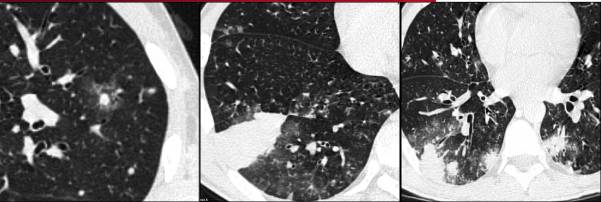

图2 骨髓移植患者的双侧肺外周实变 “晕征”。血管侵袭性曲霉病

CT表现为大小不一的结节被磨玻璃衰减影(“晕征”)环绕,以胸膜为基底的楔形实变。

晕征是指环绕实性结节或肿块的磨玻璃衰减区。这种表述来自于病理学结果,实性部分代表梗死区域,围绕的磨玻璃边缘来自于肺泡出血。疾病早期,出现晕征的可能性较高,随着时间的推移,可能会逐渐减少。